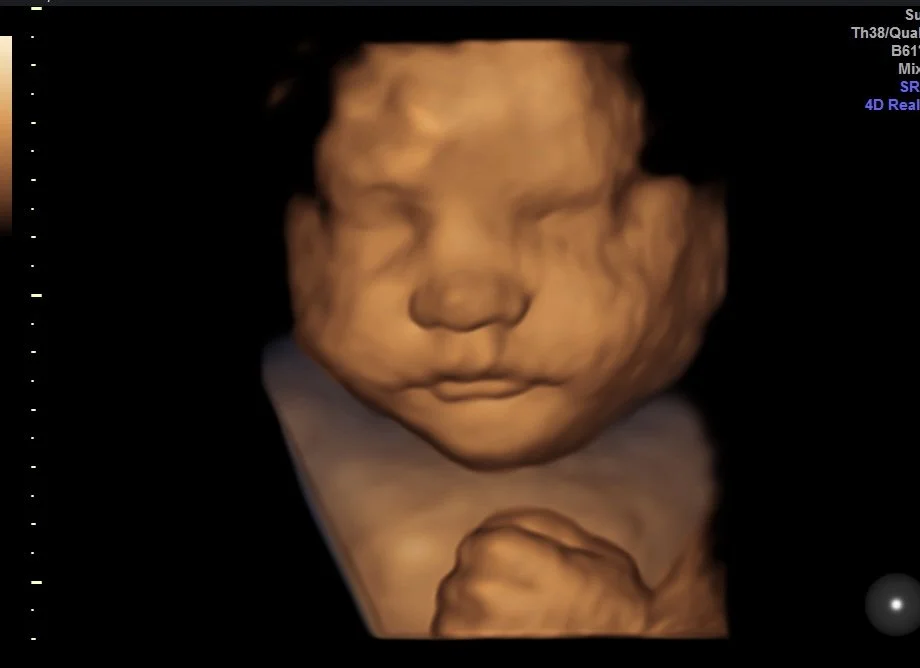

Baby Nash For Baby Of The Week

Baby Nash is 32 weeks in his 3D/4D images! He came to show off his adorable dimple & we couldn’t love it more!